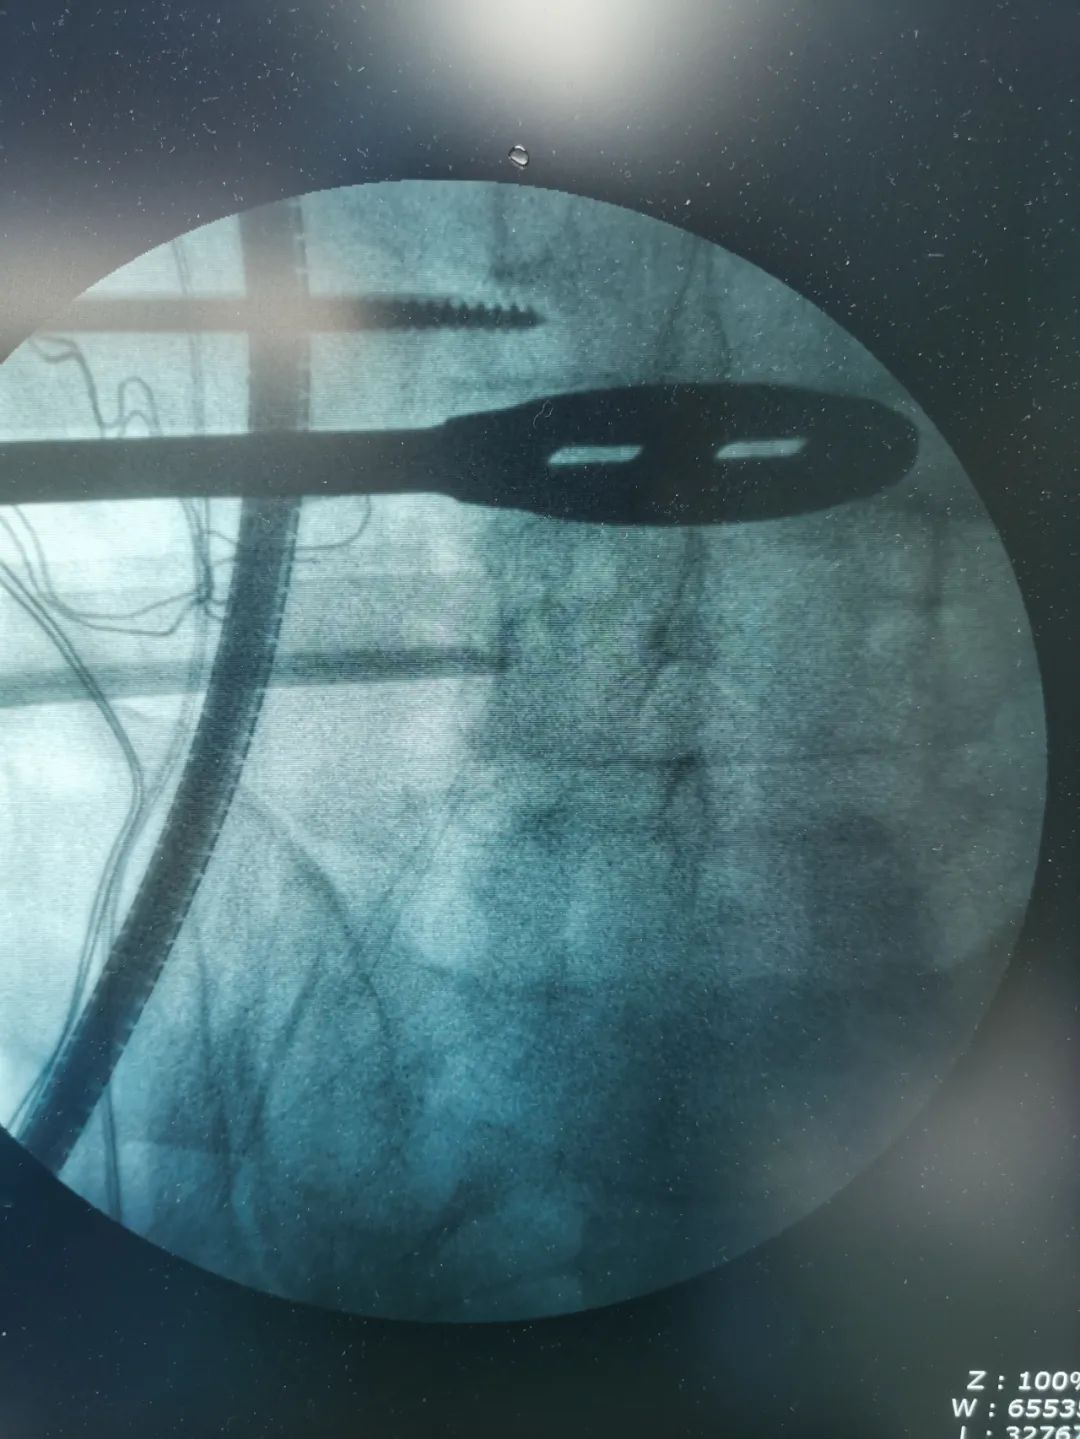

▲术中影像

经过周密细致地术前讨论及评估,由张少华主任主刀,熊东医生、手术室(麻醉科)默契配合,为李先生成功实施“OLIF腰椎微创椎体间融合术”,目的:减压,复位,融合;术中操作干净利落、精准微创,顺利完成,手术历时近4小时。